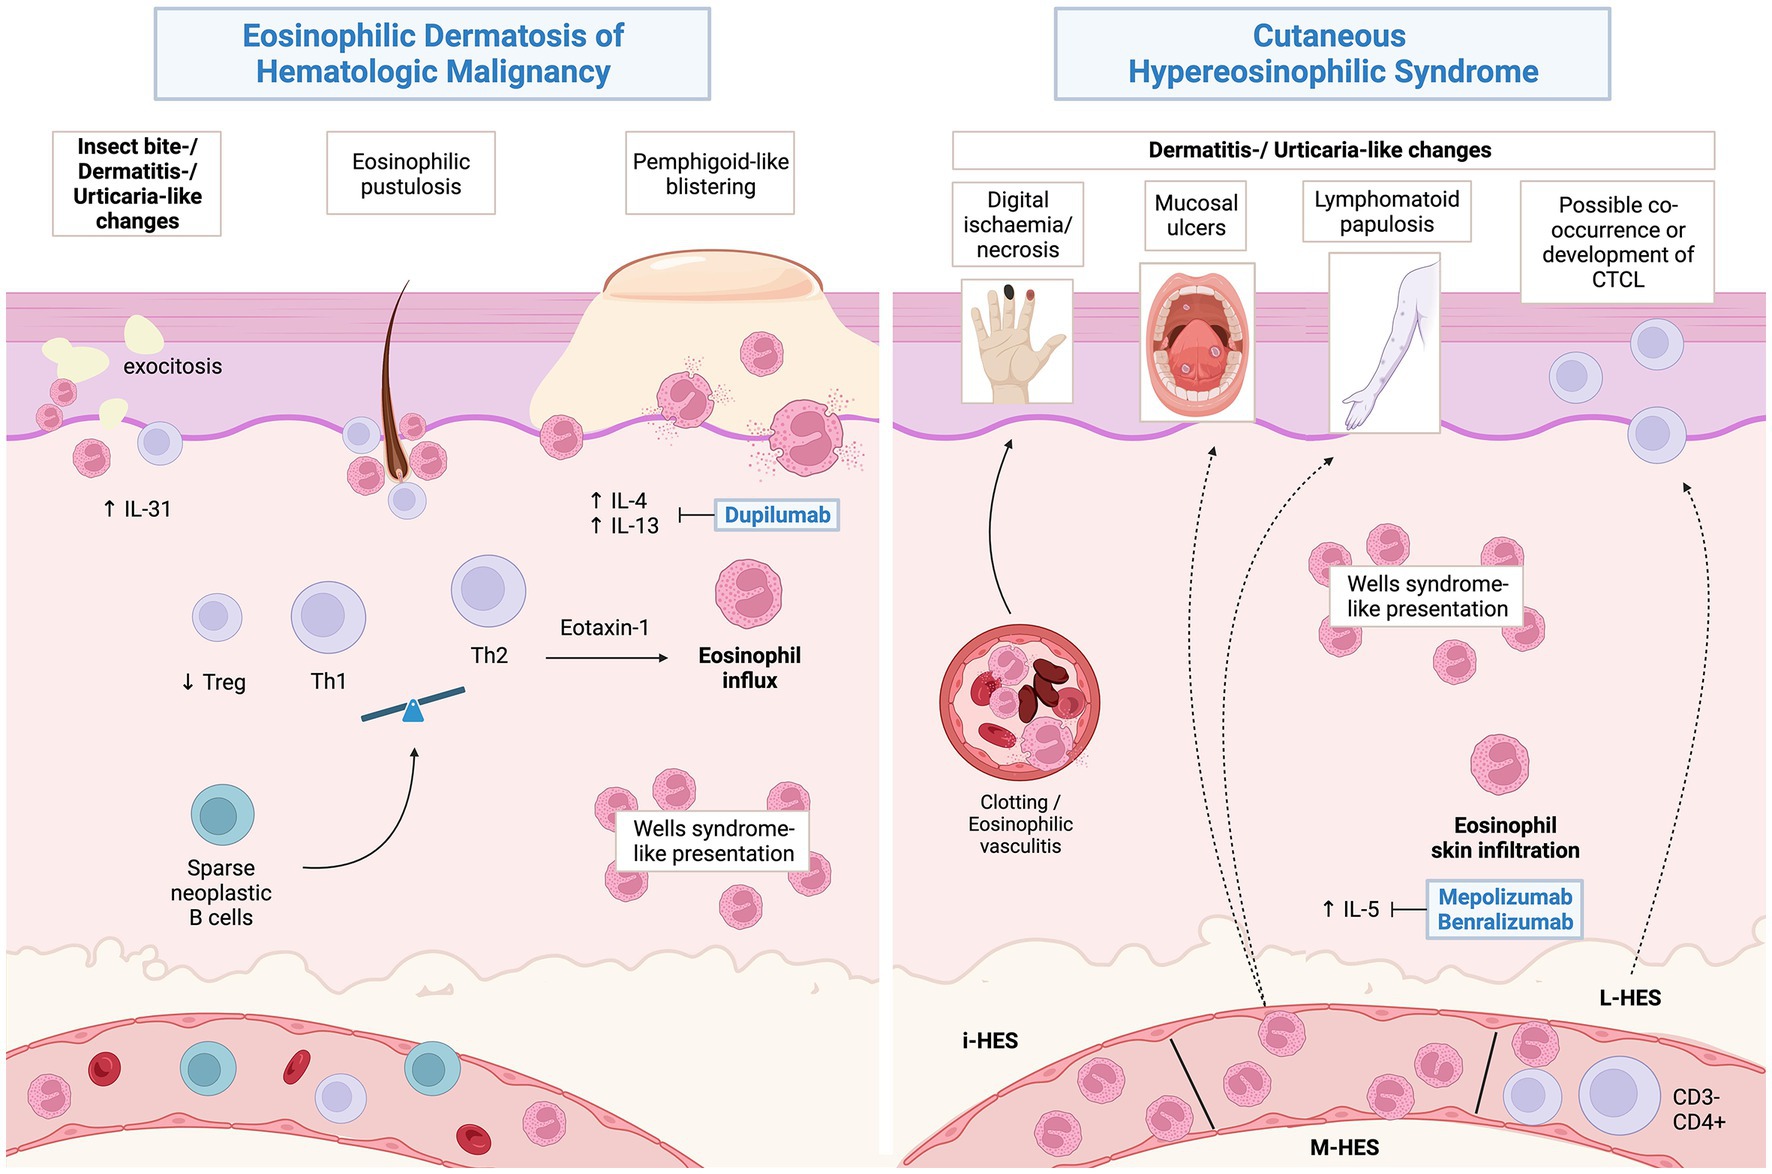

Frontiers | Neutrophilic and eosinophilic dermatoses associated with hematological malignancy

Frontiers | Neutrophilic and eosinophilic dermatoses associated with hematological malignancy